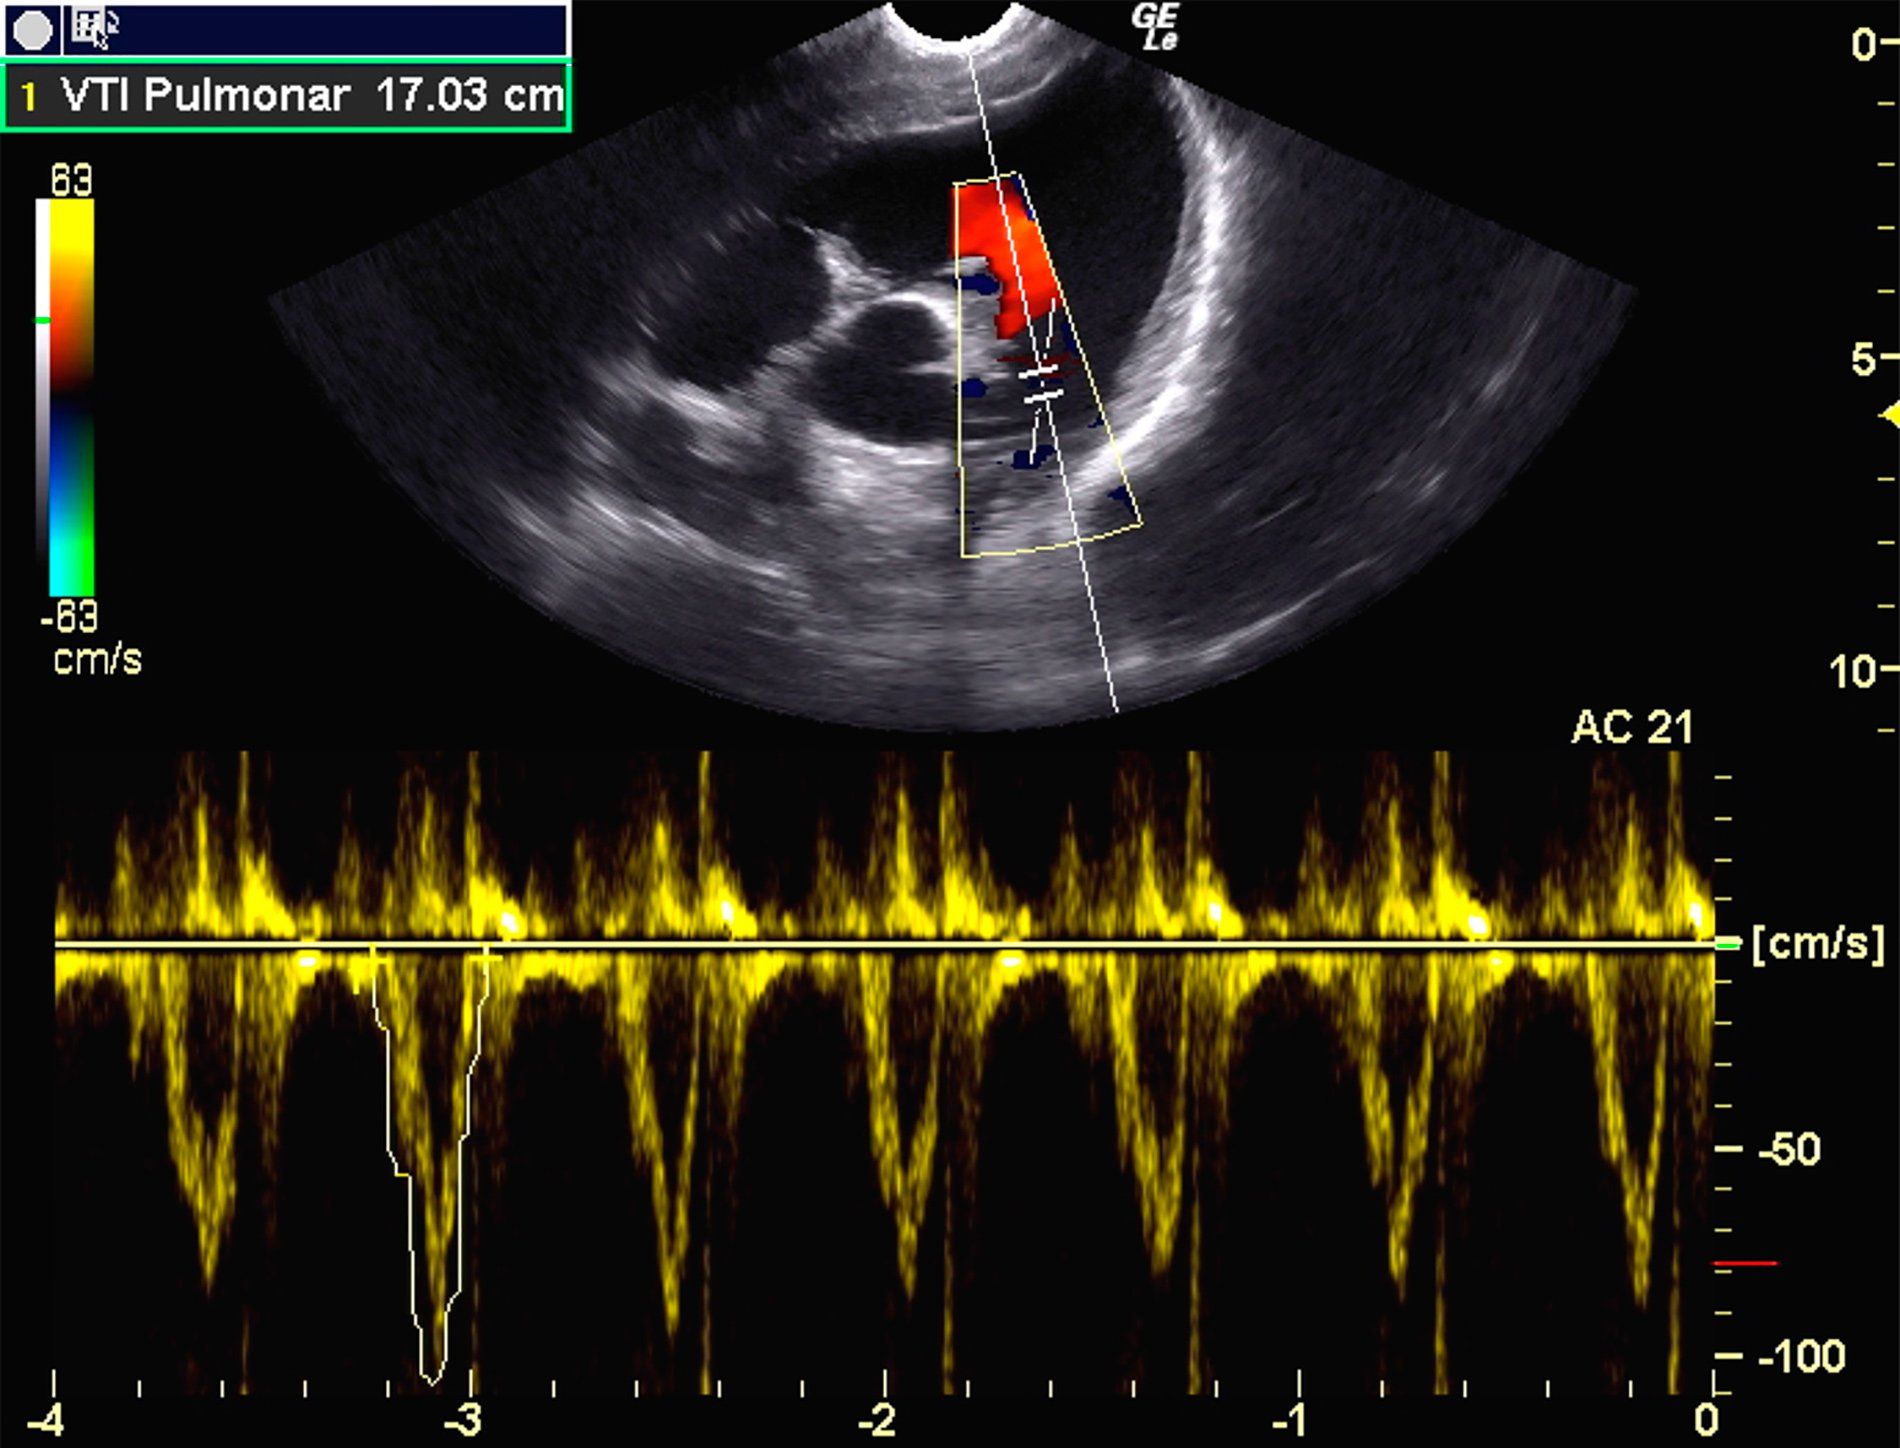

Especialidad imprescindible en nuestro servicio quirúrgico ya que anestesiar, especialmente animales mayores o con patologías graves, requiere una valoración previa del sistema cardiorrespiratorio, para establecer como, cuando y con que métodos se va a garantizar la sedación, la anestesia y la analgesia durante todo el procedimiento quirúrgico